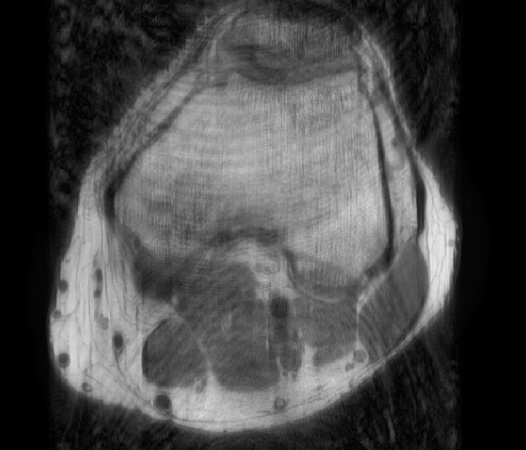

In the example below, only one fifth of the required MR radiofrequency signals is recorded. This results in a five times faster acquisition, with a subsampled k-space (top left) and inherent image artifacts after standard reconstruction (top right).

Basic compressed sensing principle

The Compressed SENSE reconstruction then uses iterative, knowledge-based algorithms to fill in the empty lines in k-space (bottom left). This removes the artifacts while keeping the final image fully consistent with the acquired data (bottom right). *Compared to Philips MR exams without Compressed SENSE